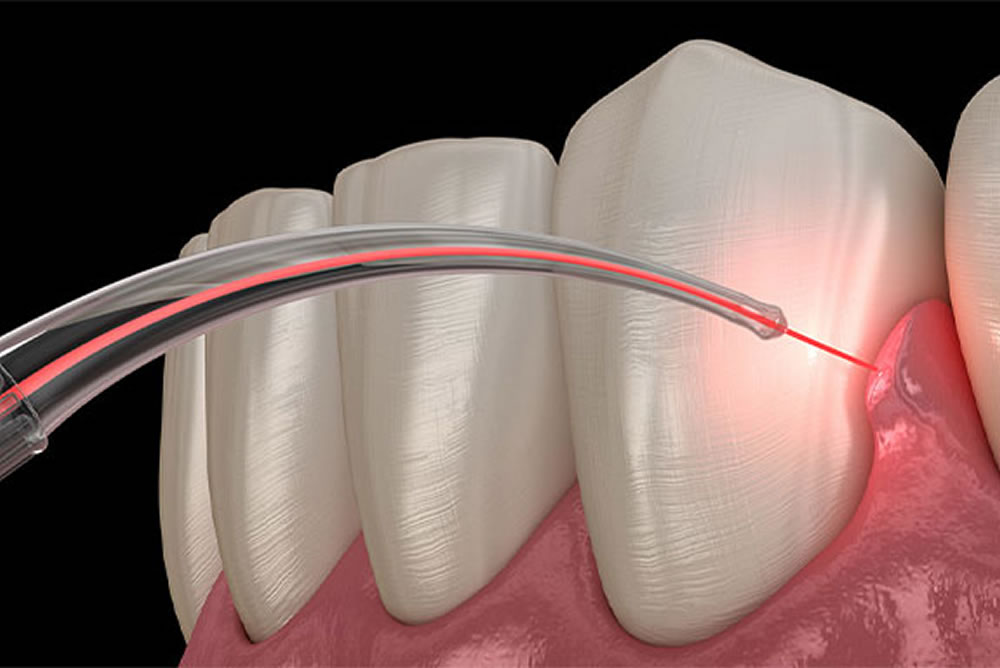

⑤ エルビウムヤグレーザーによる低侵襲な歯周病治療

BiVi歯科・矯正歯科では、エルビウムヤグレーザーを用いた負担の少ない歯周病治療も行っております。

現在、歯周病の治療で使用されているレーザーの中でも、使用時の振動や音が静かなことに加え、ほとんど麻酔を行わずに処置が行えるため、負担の少ない快適な治療が可能となります。

※当院の院長武川は歯科医師向けにレーザー治療の講演を行っております。

【エルビウムヤグレーザーの特徴】

- 痛みを抑えた処置が可能

水への吸収が非常に高く、照射した患部の表面にある水分を蒸散させ、表面部分にのみ反応するため、発熱による痛みを最小限に抑えることができます。麻酔注射もほとんど必要ありません。 - 殺菌効果・治癒促進効果がある

殺菌効果があるため、細菌の感染による疾患(歯周病・虫歯等)に効果的です。また、歯肉の切開で使用する際には、周辺組織への熱傷害が極めて少ないことや治癒を促進する効果によって、短時間で傷が回復します。 - 安全性が高い

レーザー照射による副作用はなく、電気などが流れるようなものでもありませんので、妊娠中や高血圧・ペースメーカーを使用されている方でも、治療が可能です。

エルビウムヤグレーザーの効果的な歯周病治療

歯石・バイオフィルムの除去

歯周ポケット内に付着した歯石の除去をはじめ、ブラッシングでは落とすことが困難なバイオフィルム(細菌の塊)の破壊を、痛みや不快感なく行えます。

歯周病菌の殺菌

レーザー照射によって、歯周ポケット内に存在する歯周病菌の殺菌、歯肉に残った内毒素(エンドトキシン)を無毒化し、歯周病症状の改善を促進します。

歯周病菌に感染した歯肉の切除

口臭や膿、骨の吸収の原因となる歯周病菌に感染した歯肉を、エルビウムヤグレーザーを用いて切除します。低侵襲での処置に加え、治癒促進効果によって、短時間で傷口も治ります。

⑥ 痛みや出血を抑えた外科処置が可能な半導体レーザーを完備

BiVi歯科・矯正歯科では、半導体レーザーも完備しております。半導体レーザーは痛みが少なく、止血効果が高いという特徴があります。

BiVi歯科・矯正歯科では、半導体レーザーも完備しております。半導体レーザーは痛みが少なく、止血効果が高いという特徴があります。

歯周外科治療の際などに使用することによって、痛みや出血を最小限に抑えながら歯茎を切開できるため、患者さまの負担を軽減することができます。